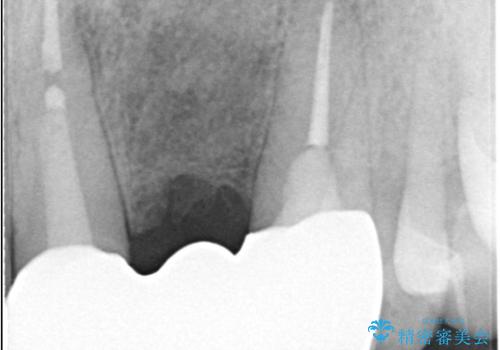

左上1番目~3番目にかけてブリッジの仮歯が入った状態で来院された患者さんで、左上3に縁下カリエスを認め抜歯してインプラントか牽引(エクストリュージョン)を行うか、歯肉根尖側移動術を行うか選択いただき牽引の後補綴処置を行うこととしました。

左上3の牽引を1か月半ほど行った後、補綴治療を行っています。

両支台歯とも根尖病巣は認められなかったため、ファイバ-コアからのやり替えとしました。